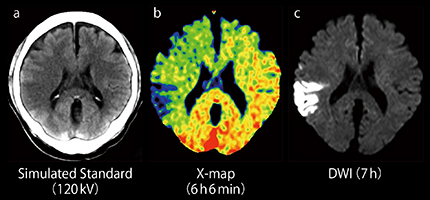

図4は,図3と同症例における120kV相当のCT画像,X-map,DWIの比較であるが,X-map ではearly CT signが非常にわかりやすい。また,120kV相当のCT画像に単純にカラールックアップテーブルを適用させた画像およびDE Bone RemovalとX-mapを比較してわかるように,X-mapは単なるカラーCT画像とはまったく異なるものである(図5)。

図4 図3と同症例における120kV相当のCT画像,X-map,DWIの比較

X-map(b)ではearly CT signが明瞭である。